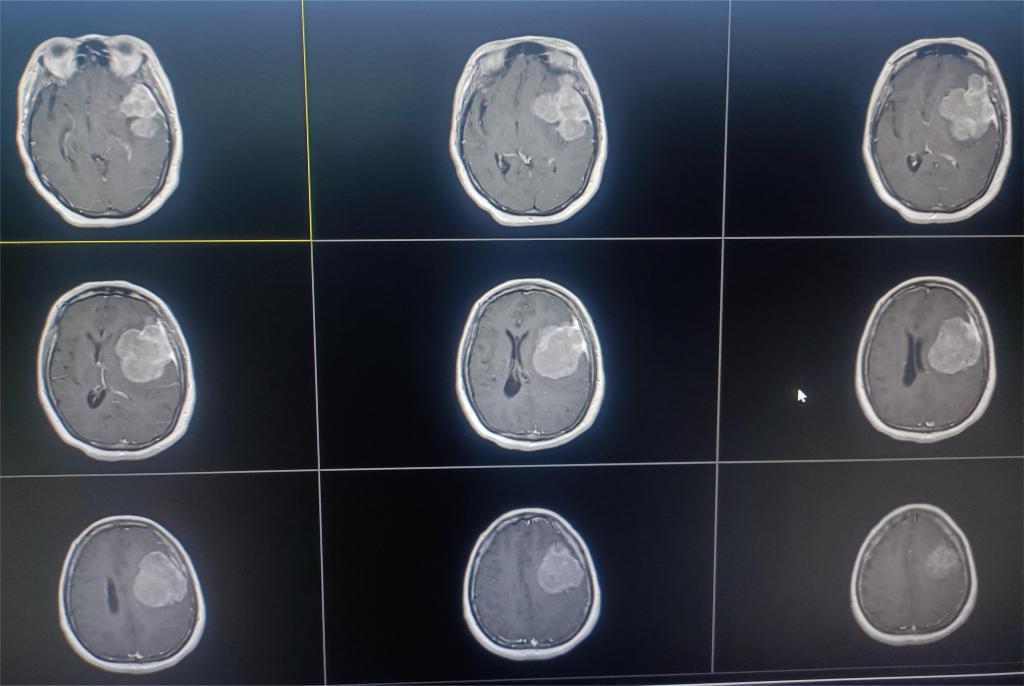

患者刘某,因“间断嘴角抽搐2周”到市中心医院就诊。行头颅磁共振提示:左侧额颞叶巨大脑膜瘤(图一)。

图一